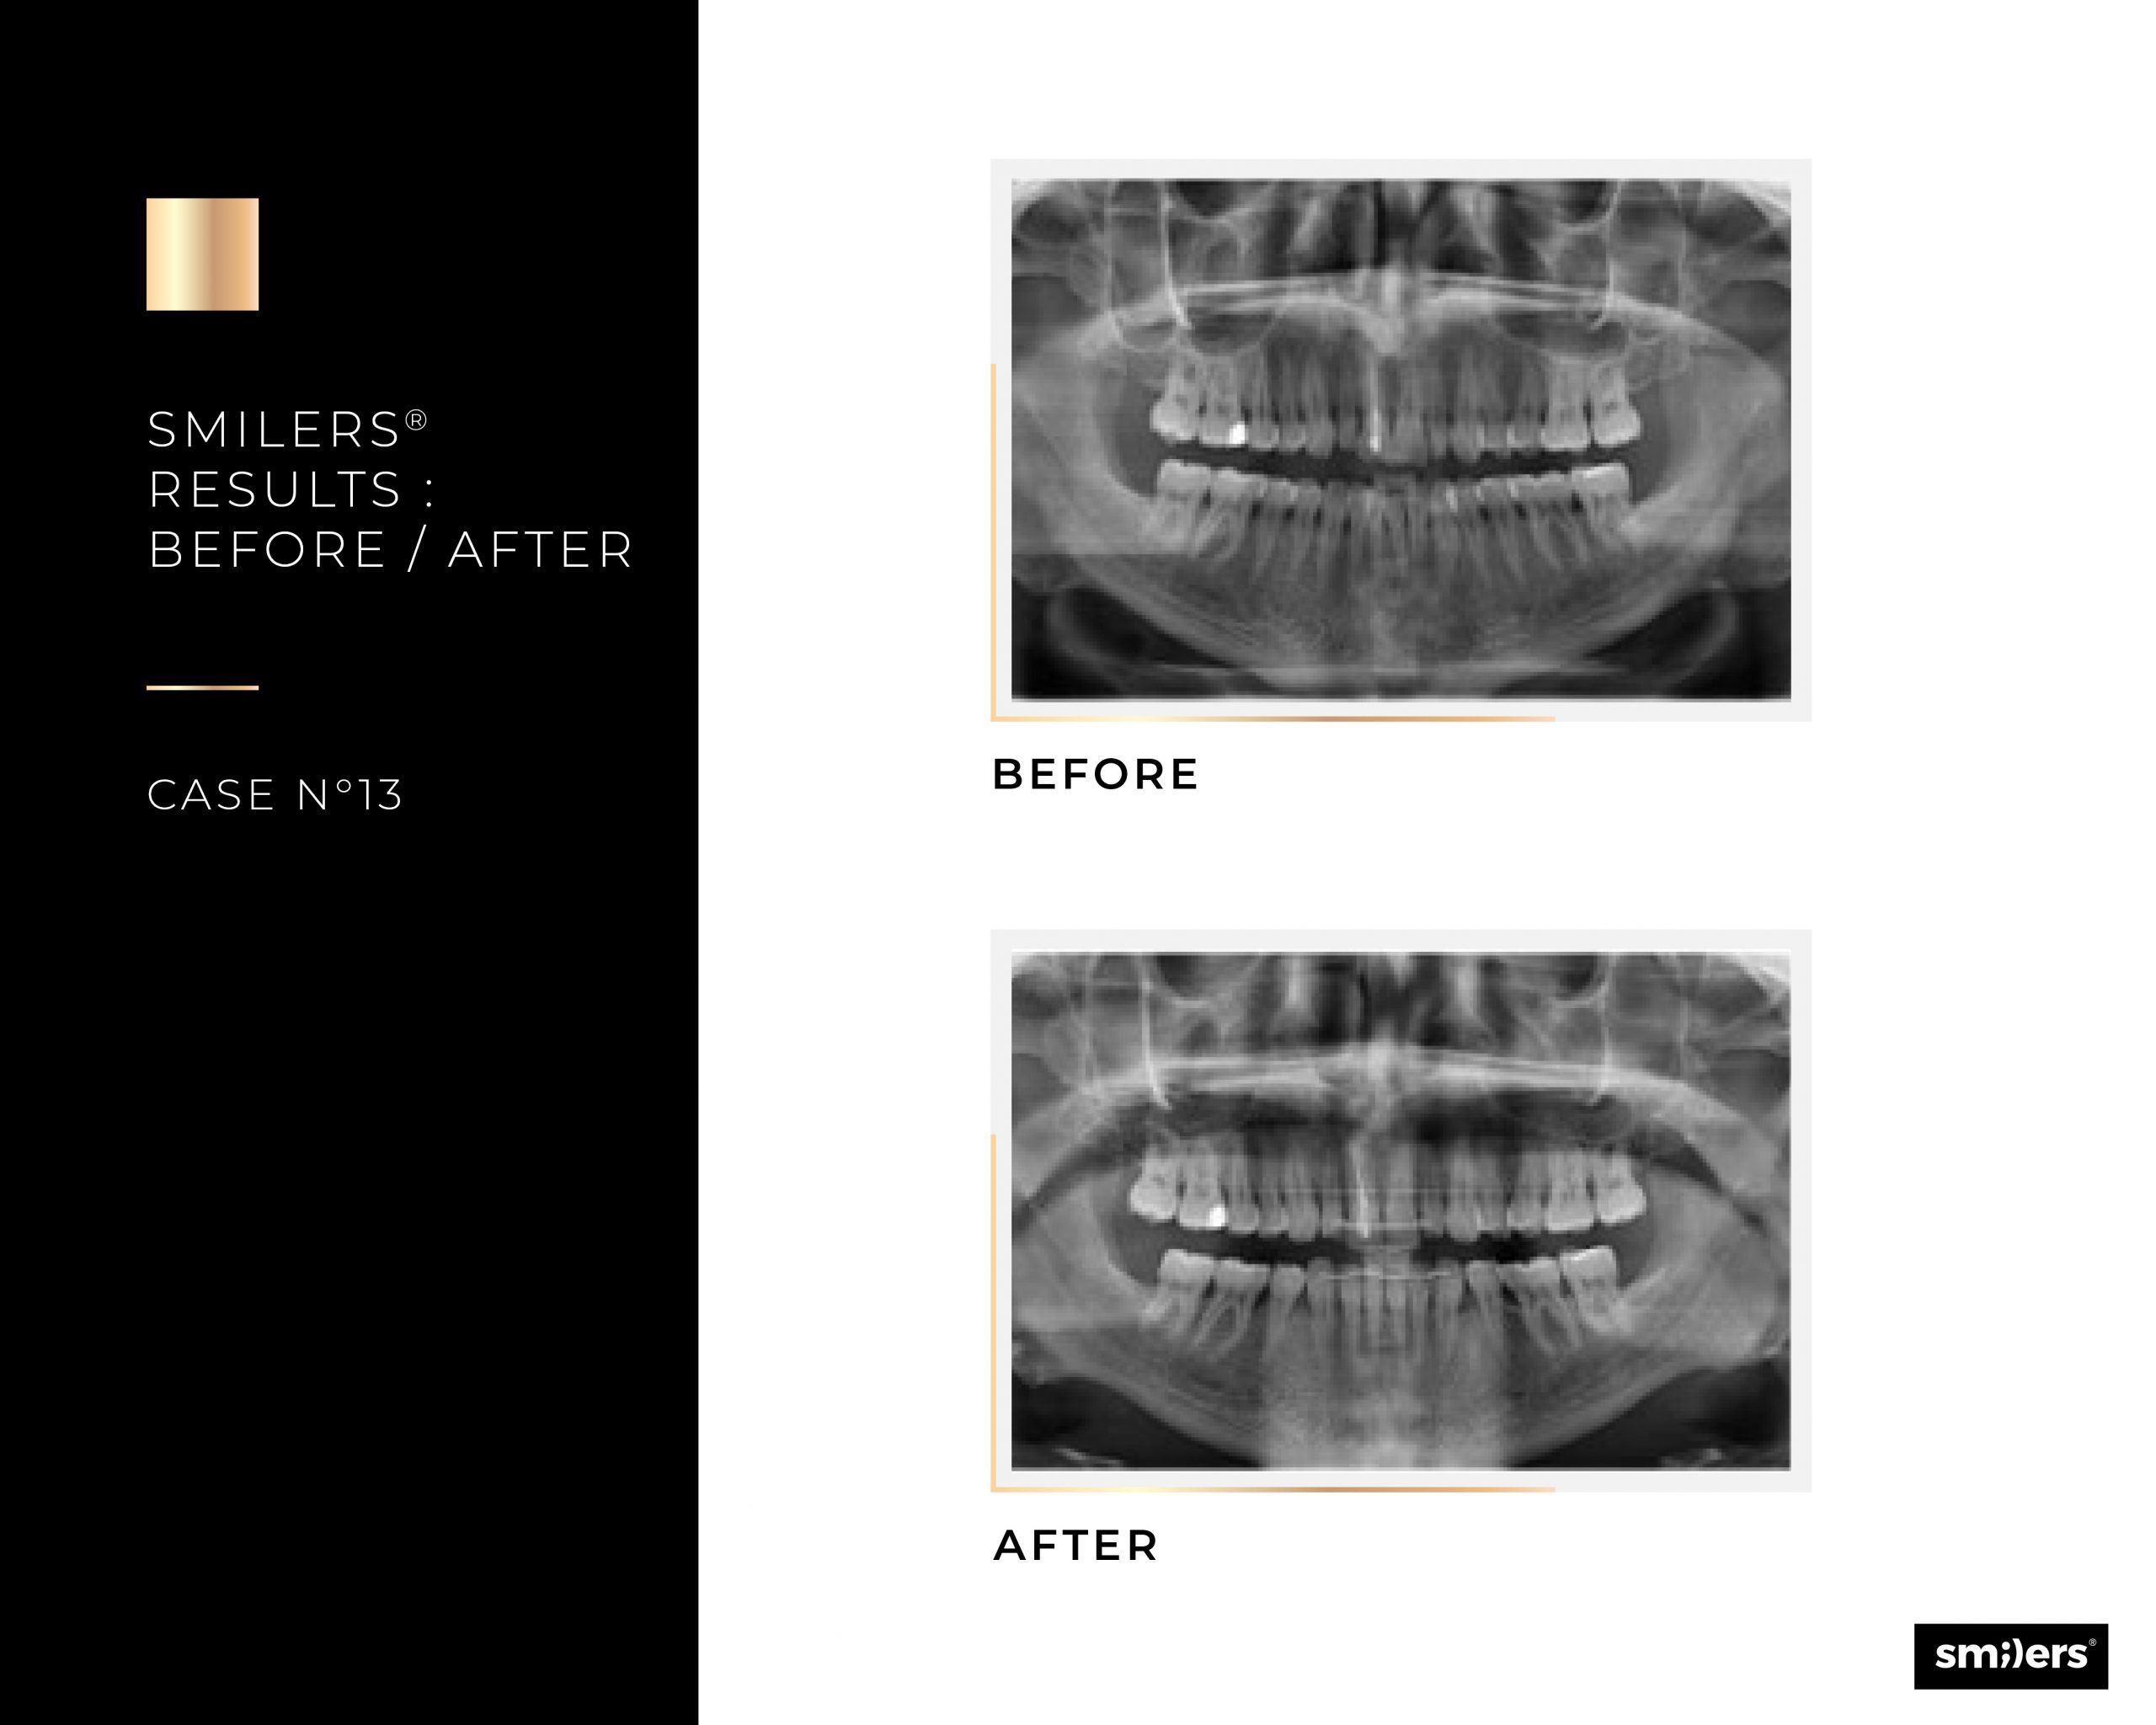

Risultati e casi trattabili